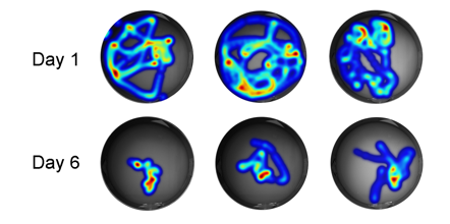

- 연구주제 : 암 성장과 종양미세환경을 조절하는 신경회로 기전연구